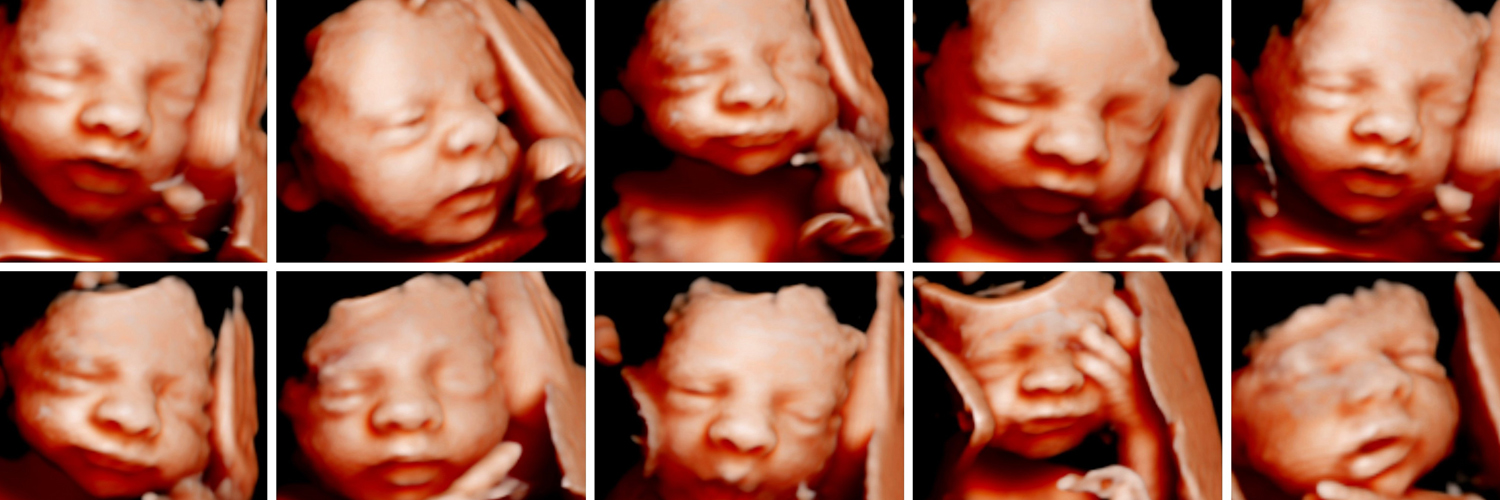

Ecografia Emocional 5D

Experiência única de conhecer o bebé antes do seu nascimento! Com a melhor tecnologia e qualidade de imagem para que possa desfrutar de uma experiência única e inesquecível.

Fazemos a revelação de sexo do seu bebé a partir das 14 semanas

Qual a melhor altura para realizar a sua ecografia?

A resposta é fácil… sempre! É sempre bonito e muito gratificante poder ver o bebé. Sabemos como já pensou várias vezes como seria bom ter um ecógrafo em casa.

Aqui podemos ajudá-la a acompanhar o crescimento do bebé!

Entre as 14-23 semanas: é a altura ideal para vermos o bebé como um todo no ecrã. Ainda tem bastante espaço e move-se muito! Vamos descobrir ou confirmar se é menino ou menina.

Entre as 23-25 semanas: O seu bebé cresce a uma velocidade alucinante… Nesta altura o rosto do seu bebé já está mais definido.

Entre as 26-32 semanas: se quer ver bochechinhas, é nesta fase! O bebé já tem as feições definidas e semelhantes com as que terá quando nascer, mas ainda tem espaço para o vermos com mais facilidade.

Mais de 33 semanas: Por esta altura o bebé já começa a ficar com espaço reduzido e na maioria das vezes os bebés já não se deixam ver muito bem … mas não é impossível … cada bebé é um bebé e por isso podemos sempre tentar captar imagens nesta fase!